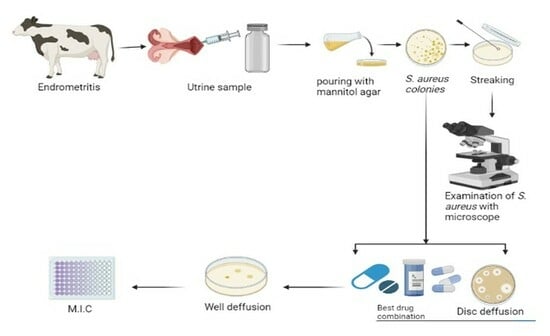

2.1. Characterization of Nanoparticles

2.2. Prevalence and Risk Factors of Endometritis S. aureus and E. coli

4.6. Uterine Sample Collection

4.6.1. Tracking Bovine Endometritis

4.6.2. Isolation of S. aureus and E. coli

4.6.3. Antibiotic Susceptibility

4.7. Evaluation of Gel Based and Nongel Based Preprations

4.7.1. Well Diffusion Assay

4.7.2. Minimum Inhibitory Concentration